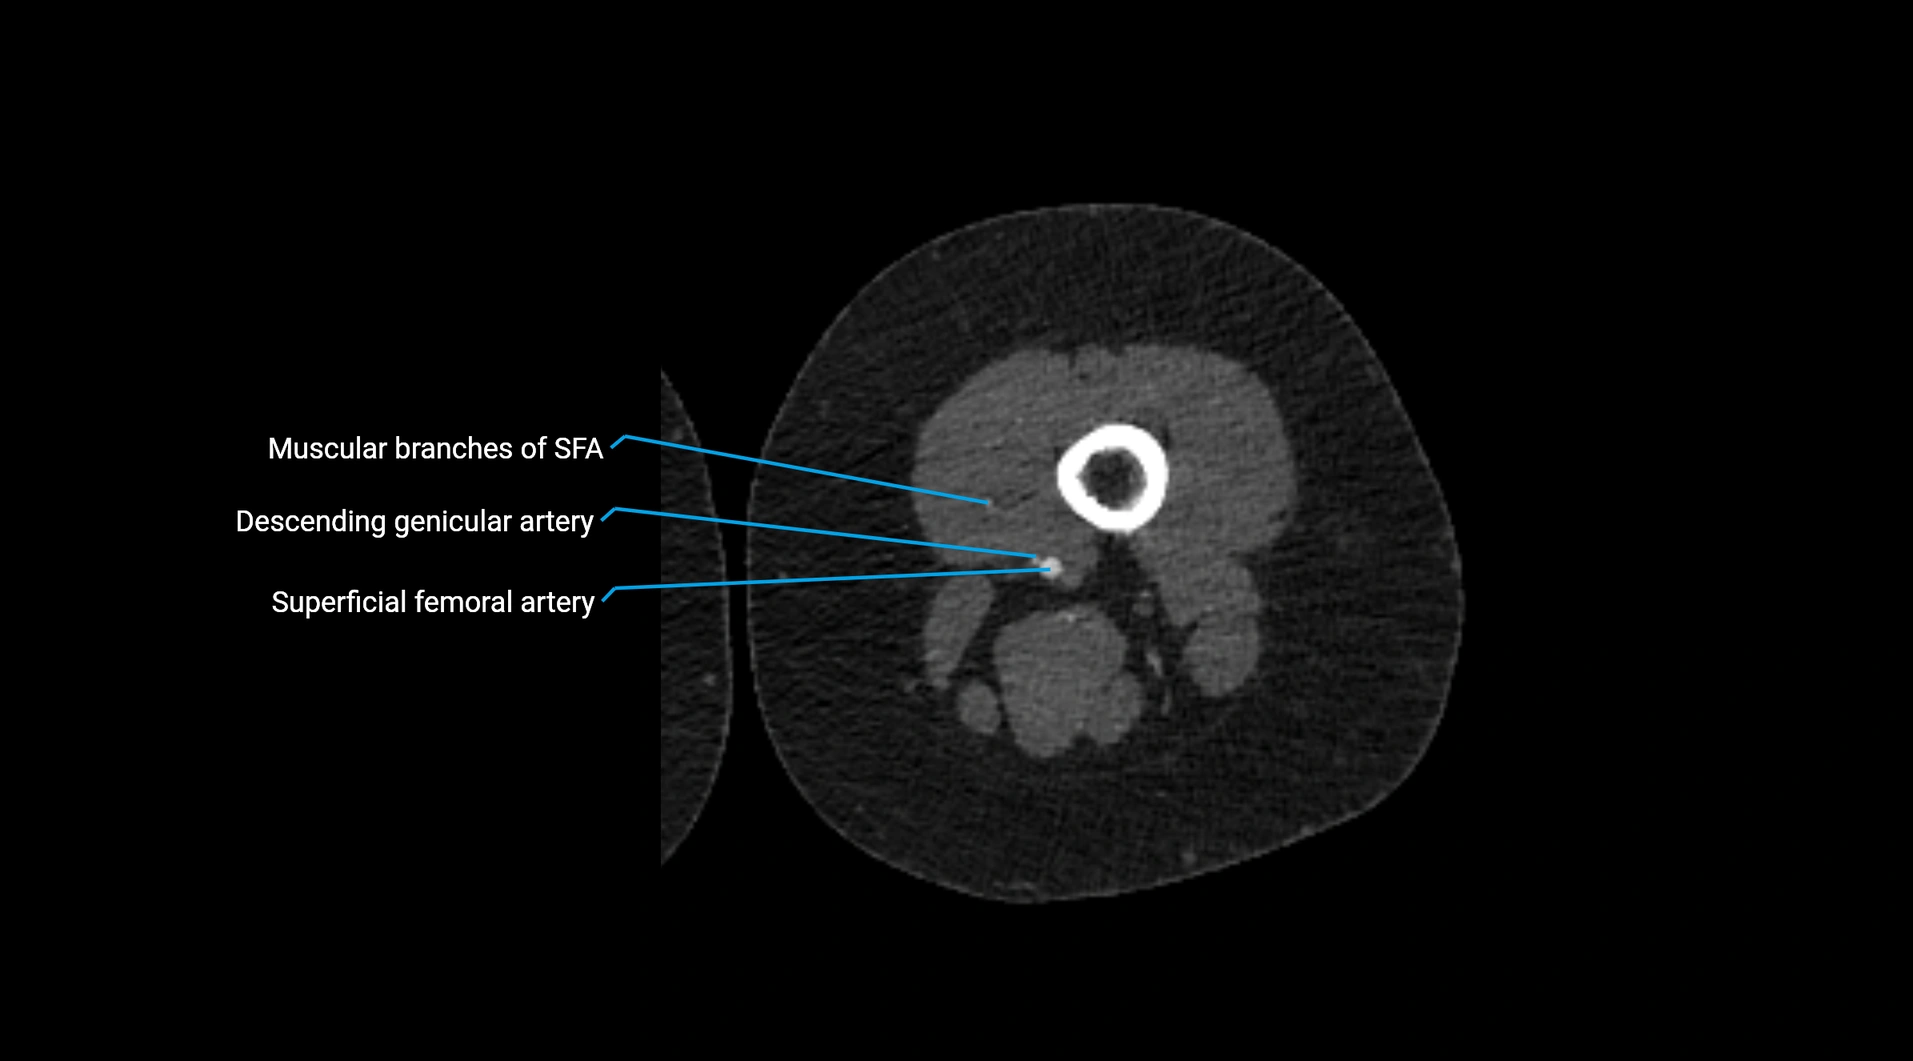

CT Appearance

Non-contrast CT:

• Appears as a tubular soft tissue structure anterior to vertebral bodies

• Calcified atherosclerotic plaques appear as hyperdense foci along the wall

• Useful for screening abdominal aortic aneurysm (AAA) size and mural calcification

Contrast-enhanced CT (CTA):

• Gold standard for abdominal aortic imaging

• Provides excellent detail of lumen, wall, aneurysm, thrombus, and branch vessels

• Multiplanar and 3D reconstructions help in aneurysm measurement, stent graft planning, and dissection evaluation

• Detects acute rupture, traumatic injury, or occlusion with high sensitivity